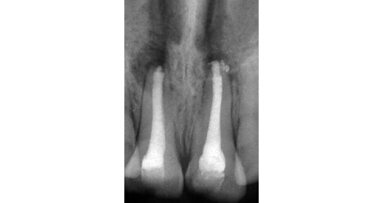

A 19-year-old male reported with a missing maxillary right central incisor. The patient gave history of trauma due to accident, which resulted in the loss of the maxillary right central incisor. On clinical examination, deficiency in the anterior residual alveolar ridge with loss of buccal cortical plate was noted. The patient was in good health and was a non-smoker with no medical contraindications for surgery, had excellent oral hygiene and a strong desire to restore the area with a fixed prosthesis. On examination there were no clinical signs of periodontitis and dental caries. Radiographically, the clinical findings were verified and revealed vertical and horizontal bone loss that was limited to the maxillary right central incisor (Fig. 2) Using the native software, non-distorted measurements were made on the cross-sectional slices to determine the dimensions of the defect within the residual socket site, and lack of facial cortical-plate as confirmed in the axial view.

After 3 weeks of additional healing, fixture level impressions were accomplished for the laboratory phase. (Impregum 3M ESPE). The final single tooth implant-supported prosthesis can be seen in Figs. 10a & b. The post-insertion radiographic image at 14 months revealed excellent bone adaptation surrounding the implant, with sufficient interproximal height of bone (Fig. 11).